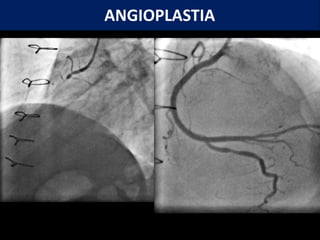

O documento descreve procedimentos de hemodinâmica como angioplastia e angiografia coronariana. Explica que a hemodinâmica estuda o movimento do sangue e é usada para diagnóstico e tratamento. Detalha a angiografia coronariana, que visualiza as artérias do coração, e a angioplastia, que trata obstruções com balões e stents.